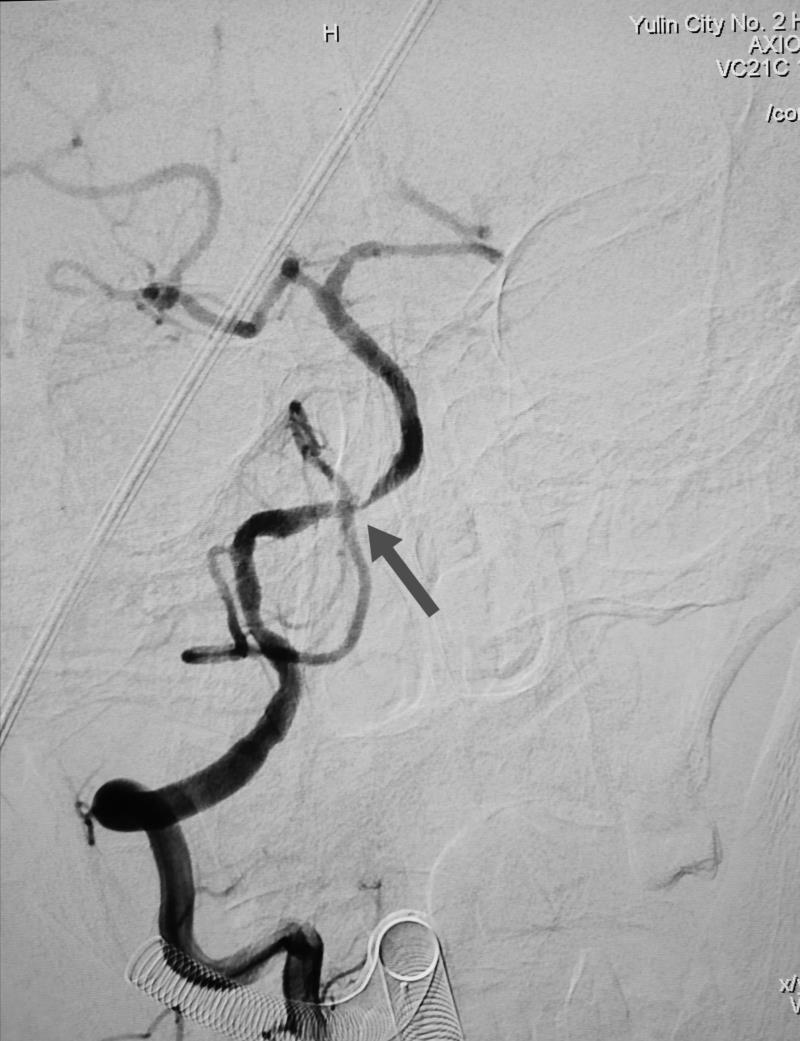

颈内动脉重度狭窄

经全脑血管造影术,发现患者右侧椎动脉V4段重度狭窄,正是病灶责任血管,同时发现右侧颈内动脉起始段重度狭窄。患者王某的情况岌岌可危,这两处血管狭窄随时可能闭塞,一旦闭塞,轻则出现严重残疾,完全丧失生活能力,重则很快危及生命,他的椎动脉远端狭窄处介入手术风险异常高,手术过程中很可能发生急性血管破裂或栓塞,形成严重的脑干出血或者梗死,造成死亡。患者右颈内动脉狭窄处于颈动脉窦部,是人体血压和心率的感应器,非常敏感,加之该患者平时就有心率缓慢的情况,术中很有可能心脏停搏造成死亡。